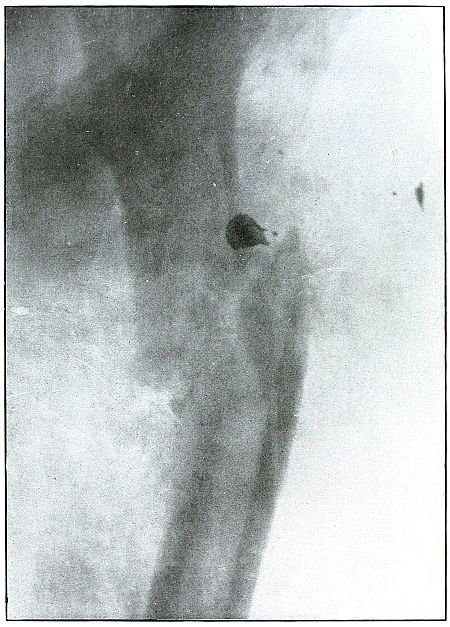

Plate 57.

[Pg 125]

Rifle—Plate 57.

LOWER EXTREMITY.

Gunshot Fracture About the Middle of the Femur,

with Lodgment of the Fragments of a Deformed Bullet.

The course of the missile was transverse. All of the remaining energy

of the retarded velocity of the short range of a ricochet shot was

stopped by the bone with the result of a long splitting fracture, and

the lodgment of one large and a few small fragments of the missile.

The small notched metal fragment lying to the right of the upper

bone fragment is a small bent piece of the jacket, detached from the

greatly deformed lead core, which can be faintly seen lying behind the

lower end of the left side of the upper bone fragment.

The treatment is extension with lateral compression, although this